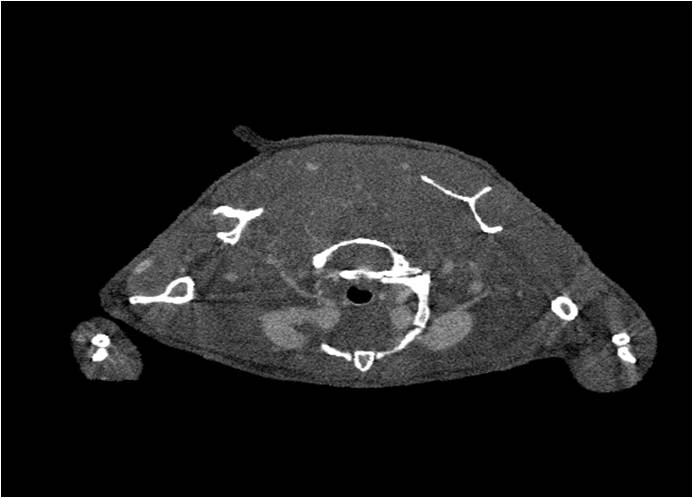

腫瘤血管生成

肺纖維3.jpg

肺轉移

小鼠模式,22.5μm像素

正常

正常.jpg

8天                                                                  14天

8天.jpg  14天.jpg

無(wú)造影劑注入                                     造影劑注入